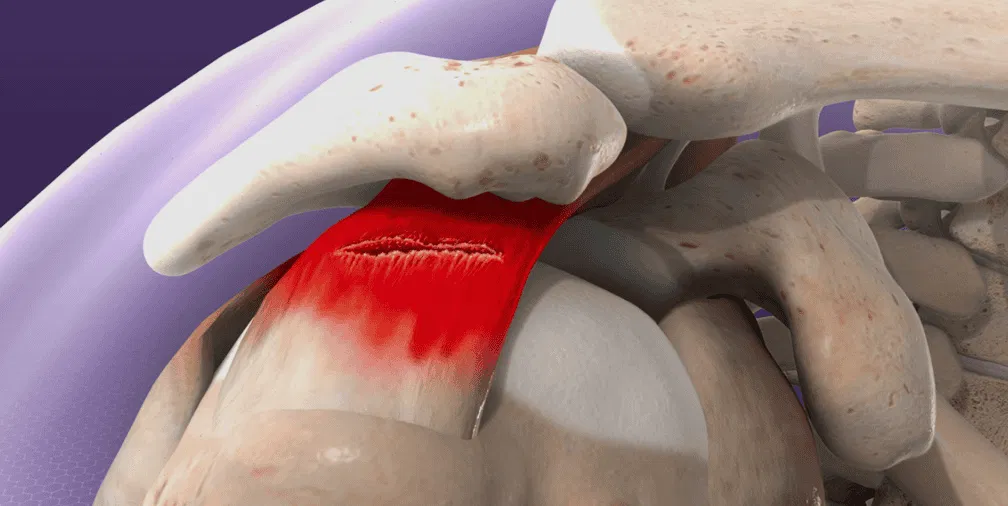

An MRI scan is the gold standard for visualising soft tissue structures including the meniscus, and can confirm the location, type, and severity of a tear. A weight-bearing x-ray may also be helpful to rule out bony involvement or assess for arthritic changes.

Hyaluronic acid injections to improve joint lubrication and reduce pain in those where articular cartilage changes or patellofemoral joint degeneration accompany the running injury.